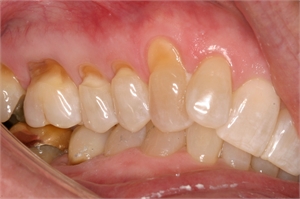

Close-up photograph of abfraction lesions and the gum margins

Tooth abfraction appears around the gum line as minuscule wedges or grooves.

Tooth abfraction appears as enamel wear  at the cemento-enamel junction (CEJ)

In simplest words, abfraction can be described as breaking away. It is characterized by minuscule wedges or grooves at the cemento-enamel junction (CEJ) or the neck of the tooth at the gum line. These are thought to occur due to biomechanical loading. In other words, these are due to excessive force generated while chewing and by oral habits like bruxing. There is a lot of controversy regarding the existence of this process but sufficient evidence is present that points towards it.